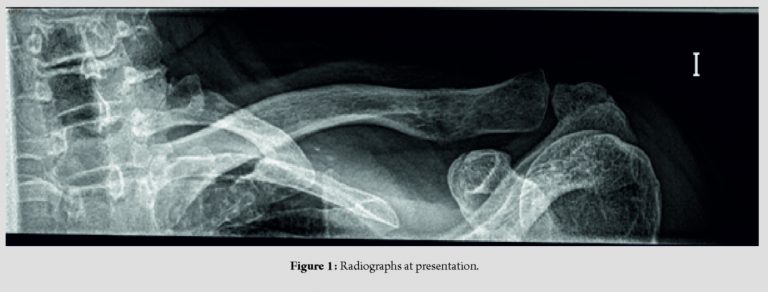

On examination, there was a significant pain on palpation in the distal third of the clavicle and acromioclavicular joint. Limited active range of motion (abduction of 100°, anteflexion 90°, external rotation of 20°, and internal rotation up to L3), and abnormal rotator cuff strength (4 of 5).There was no vascular or neurologic deficit. Standard two-dimensional radiographs were taken (Fig. 1), with an abnormal fracture of the lateral third of clavicle without clear traumatic history. Magnetic resonance imaging showed a fracture in the lateral third of clavicle accompanied by a soft tissue mass and bone edema (Fig. 2).